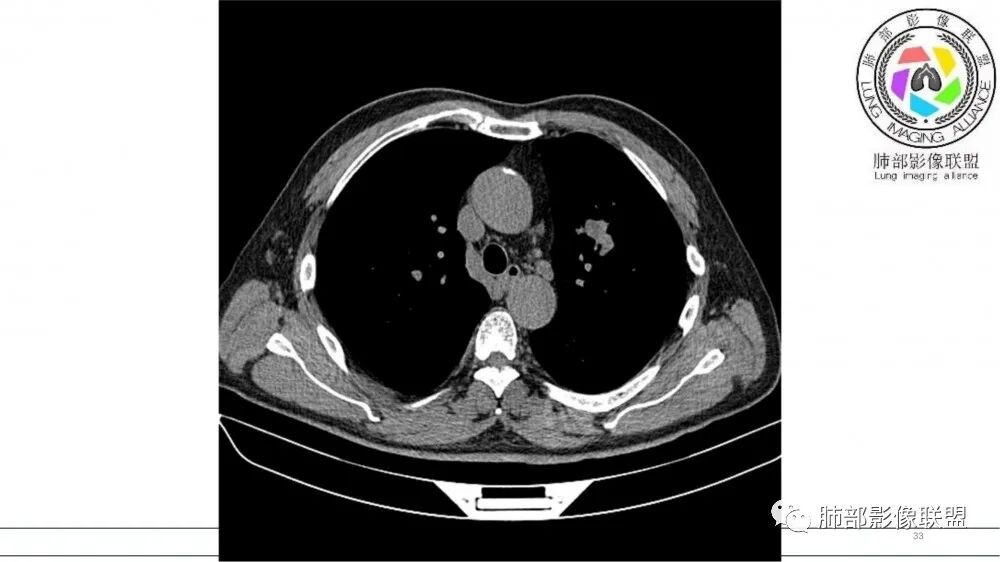

左肺上叶前段支气管内铸形生长软组织影,增强后均匀强化,远侧见斑片状磨玻璃影。考虑恶性病变,粘表?粘液腺?

老年男性,左肺上叶前段支气管内铸形阴影,增强后病灶不均匀强化,内部有坏死?远端可见斑片状阴影(阻塞性肺炎)。考虑恶性病变,老年人,鳞?类癌?粘表不能排除。

男,70岁,吸烟史,咳嗽,胸闷憋气一个月,左肺上叶不规则形软组织密度影,病灶沿支气管走形,周围见粟粒及棉絮样稍高密度影,增强扫描病灶内见少许坏死,考虑鳞癌可能,鉴别结核。

老年男性,肺气肿,吸烟史,左肺上支气管腔内铸型高密度影,呈指套状,远端多发树芽,增强不均匀强化,考虑鳞癌,鉴别小细胞癌

B3指套征,常规不是鳞癌就是ABPA,有强化丶血管造影征,倾向于鳞癌

2021年8月6日晨读病例结果:小细胞肺癌

研究报道,中心型 SCLC 经 CT 扫描后通常支气管表现为鼠尾样狭窄,肺门或纵隔肿块明显,由于肿块沿管壁生长表现为顺延支气管形态的不规则形状。病灶相对特征性影像学表现比如鸭蹼状、腊肠状、葫芦状及葡萄状改变,可以出现血管包埋,很少有空洞、空泡,较少引发肺不张,阻塞性炎症成都较轻。与一般肺癌比较,恶性程度高,侵袭力强、病灶很小就容易远处转移!Herzberg 等[19]研究指出,20%以上 SCLC 倍增时间短,预后不良。